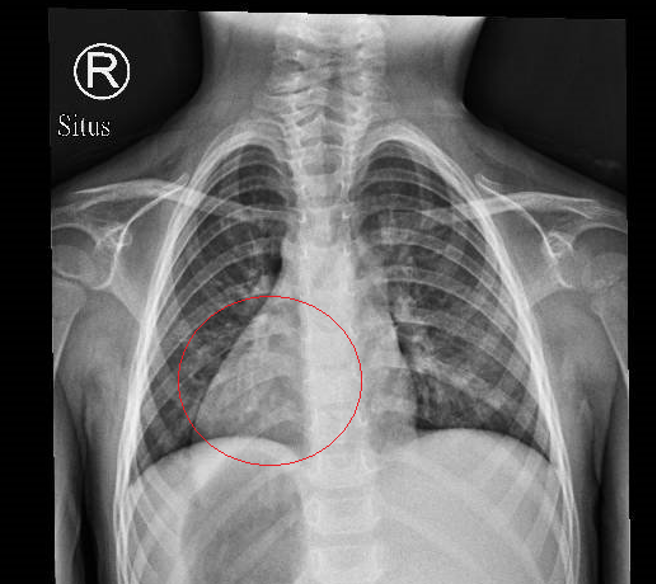

彰化一名3岁女童日前因发烧、咳嗽到部立彰化医院就医,小儿科主任马瑞杉看X光片确认女童罹患肺炎,但他从X光片意外发现,女童的心臟长在右侧,连其他内臟也都左右相反,是「完全性内臟异位」个案,即俗称的「镜面人」,发生机率小于万分之一。

马瑞杉今(26)日表示,替女童照X光片确诊是肺炎,马上要求住院,但让他吓一跳的是,女童的心臟左右调转,再经超音波等检查发现,其他内臟也全都左右异位,让他一度以为是影像上传错误。

马瑞杉说,一般人的肝臟在右上腹、脾臟在腹腔的左上方、胃在左上腹,但女童的肝臟和脾臟位置对调、胃在右上腹,而一般人在右下方的盲肠,女童则变成在左下方,其他如肺臟、大血管等位置也都左右对调。

马瑞杉表示,临床上器官转位主要分为2种,只有心臟在右侧,其他内臟器官位置正常,称为「右位心」,另一种是如女童这种罕见个案,被称为「完全性内臟异位」(situs inversus totalis),内臟全部左右相反,呈镜像样态,其机率小于万分之一。